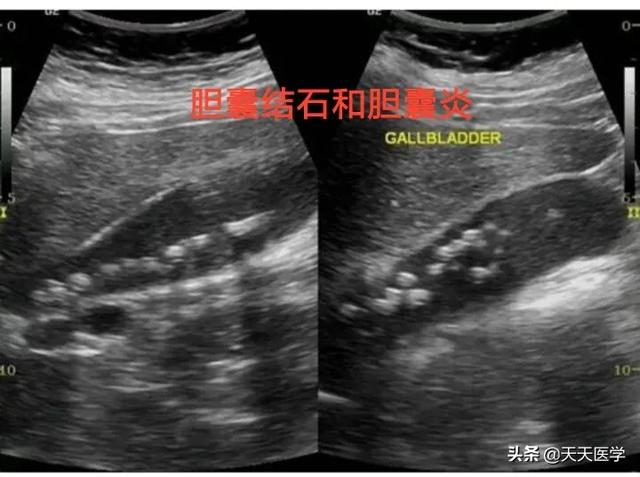

胆石が疑われる場合、私たちは超音波検査を受け、基本的に診断することができ、非常に高い精度で、95%以上の胆石患者を見つけることができる今、地域の病院が非常に発達しており、超音波で胆石を診断することができる。

上の写真は、胆嚢内に大小複数の結石を認める超音波所見である。

胆嚢結石は一般的で無症状ですが、半年に一度は超音波検査などの定期検診を受けることをお勧めします。超音波検査による胆嚢結石の発見率や診断精度は90%以上であり、検査費用も手ごろである。慢性的な痛みを繰り返す症状がある場合は、胆嚢摘出術を考慮する必要がある。